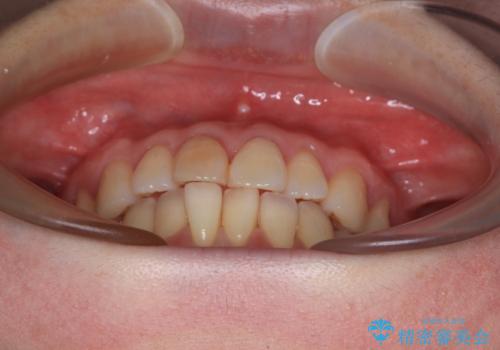

前歯のデコボコをインビザライン・モデレートで矯正治療

- 上下前歯のデコボコを気にして来院された患者様です。

安価なインビザラインパッケージを用いての治療を希望されており、デコボコの程度が中等度であったため、インビザライン・モデレートを用いて矯正治療を行うこととしました。